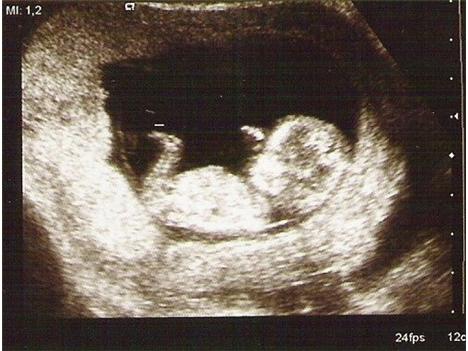

takto vyzera dieta v 12. tt a tvoj priatel povie ze to nie je este babatko? Mne to ako babo rozhodne pripada... (neviem v kt. tyzdni si ale v 12. sa potrat este legalne vykonavat moze)